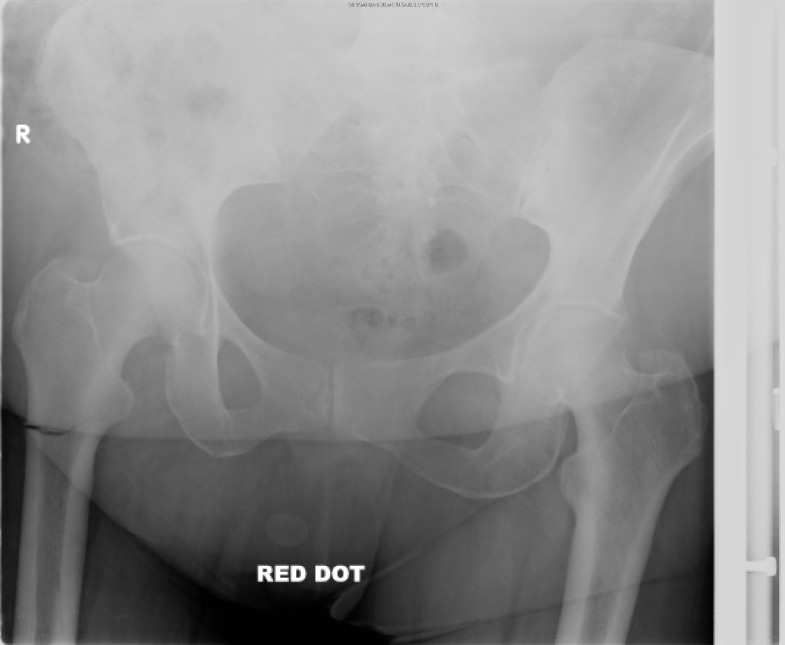

Spontaneous transverse fracture of right femur in a girl aged 10